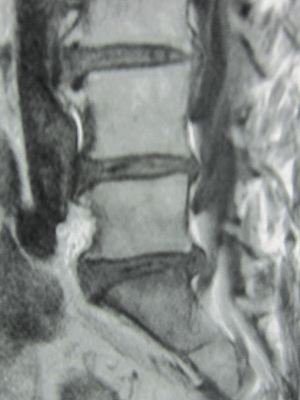

病院で検査してもらったところ「L4とL5椎間板髄核は脱出がみられ、脊柱管狭窄を呈しています」とのこと。

病院でMRIを撮ってもらったところ「椎間板ヘルニアによる坐骨神経痛」と診断された。